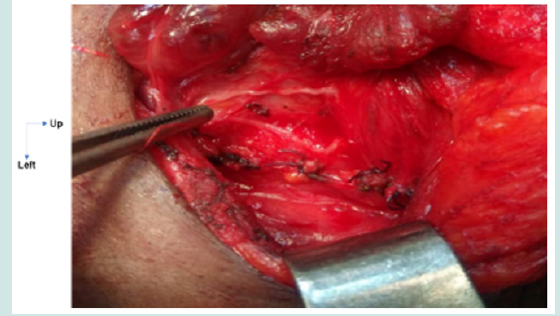

Figure 3: Bifid ILN.